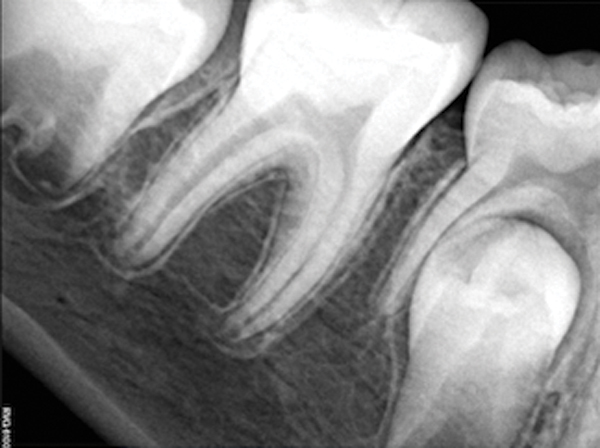

Fig 1. through Fig 3. Root filled with bioceramic sealer cut at different distances from the apex (Fig 1 through Fig 3: 0.5, 1.5, and 3.0 mm). One gutta-percha point is used as a plugger to move the sealer using hydraulic pressure. Note the irregularities are very well filled.

Pre-mixed BC Sealer is the only pure medical-grade bioceramic product available as a sealer for endodontic obturation. It has the same basic chemical composition as the other pre-mixed bioceramic products, but it is less viscous, which makes its consistency ideal for sealing root canals. It is used with a gutta-percha point, which is impregnated on the surface with a nano particle layer of bioceramic. The gutta-percha is used primarily as the delivery device (plugger) (Figure 1 through Figure 3) to allow hydraulic movement of the sealer into the irregularities of the root canal and accessory canals (Figure 4 and Figure 5).